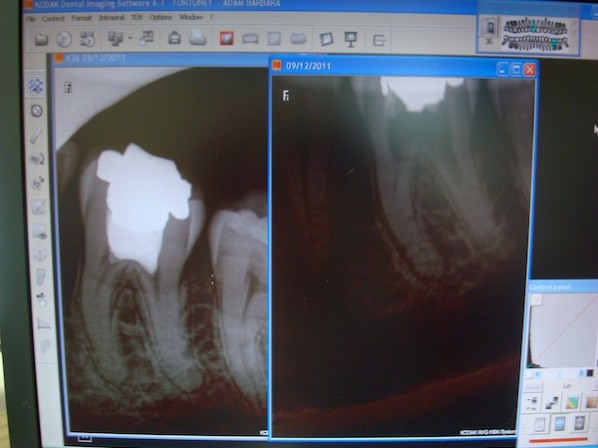

Tooth Bomb

The time bomb in my mouth finally exploded. For more than 20 years I’d been warned this could happen and urged to take action. But for more than 20.